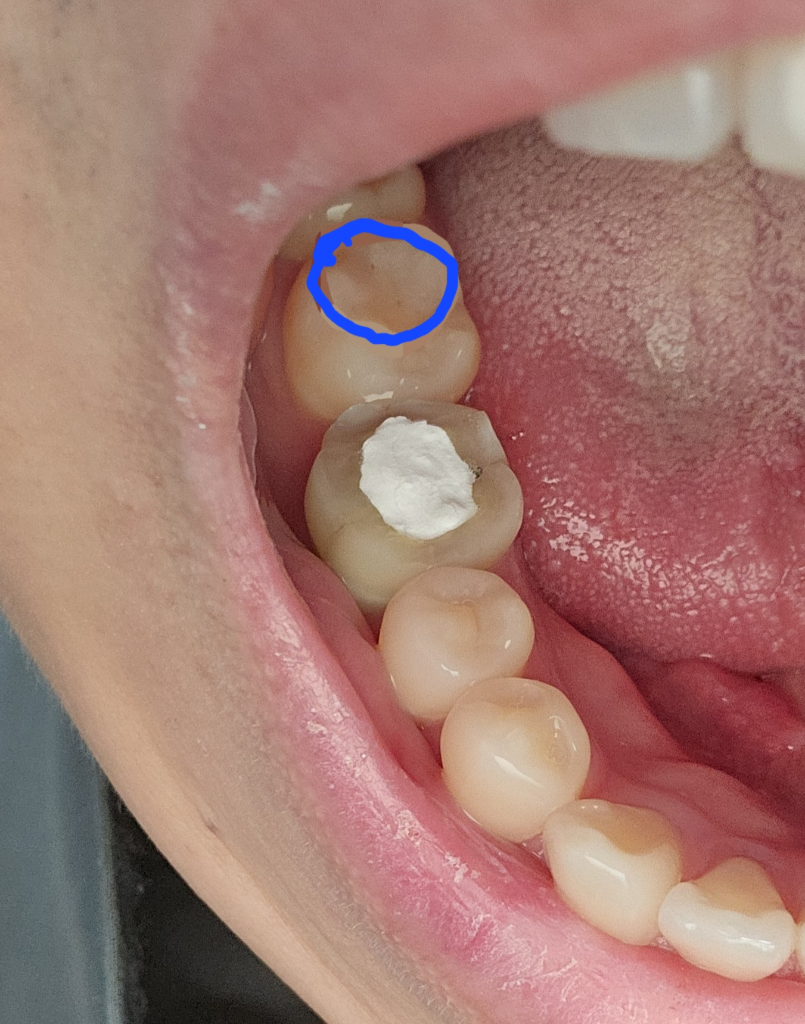

크라운 하기에는 조금 애매합니다. 크라운은 전체적으로 씌우는 것이니 치아 전체를 삭제해야 하니 조금 아까운 느낌이 있습니다. 인레이만으로 해도 가능할 것으로 보입니다.

치아가 깨지신거 같네요 . 저정도 깨진상태이고 증상이 없다면 인레이를 하셔도 될것같습니다.

보통 치아에 운전면에 파절이 생기거나 충치가 있다면 인접면의 모양을 수복해 주기 위해서 인내이 치료를 하는 경우가 많습니다.

해당 부위가 불편하지 않고 한 범위가 넓지 않다면 레진으로 충전 치료만 할 수도 있습니다 자세한 확인을 위해서 치과에서 진료를 받아 보는 것을 권유 드립니다